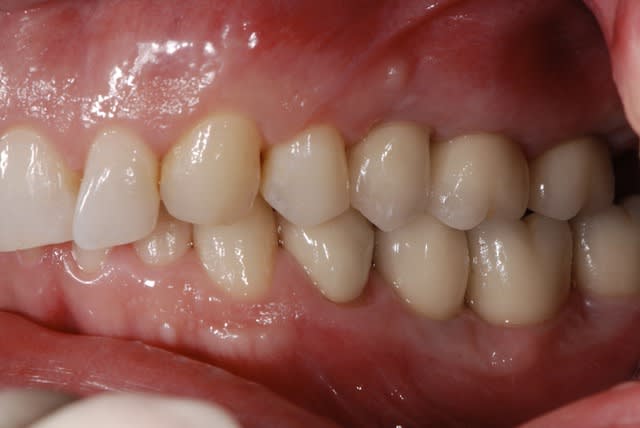

Le support paro est stable depuis 3 ans et la maintenance parfaite. je pense ici qu'un traitement ortho serait une bonne solution. j'ai déjà effectué un traitement similaire sur une 12 égressé ( confère photo ci-joint) et même si comme certain l'ont décrit, on a quelques aléas a cette méthode, ca vaut le coup d'essayer.

Elle est en pleine forme cette 11, pas de mobilité un bel os, je vais essayer de la garder, sinon si ça marche pas, ben on l’enlèvera, en attendant je vais lui laisser sa chance.

l'aspect de la gencive en vestibulaire de la 11 me fait penser que l'os est fin et cortical , je ne ferais surtout pas d'ortho sur cette dent et je solutonnerai le problème esthétique par un facette céramique